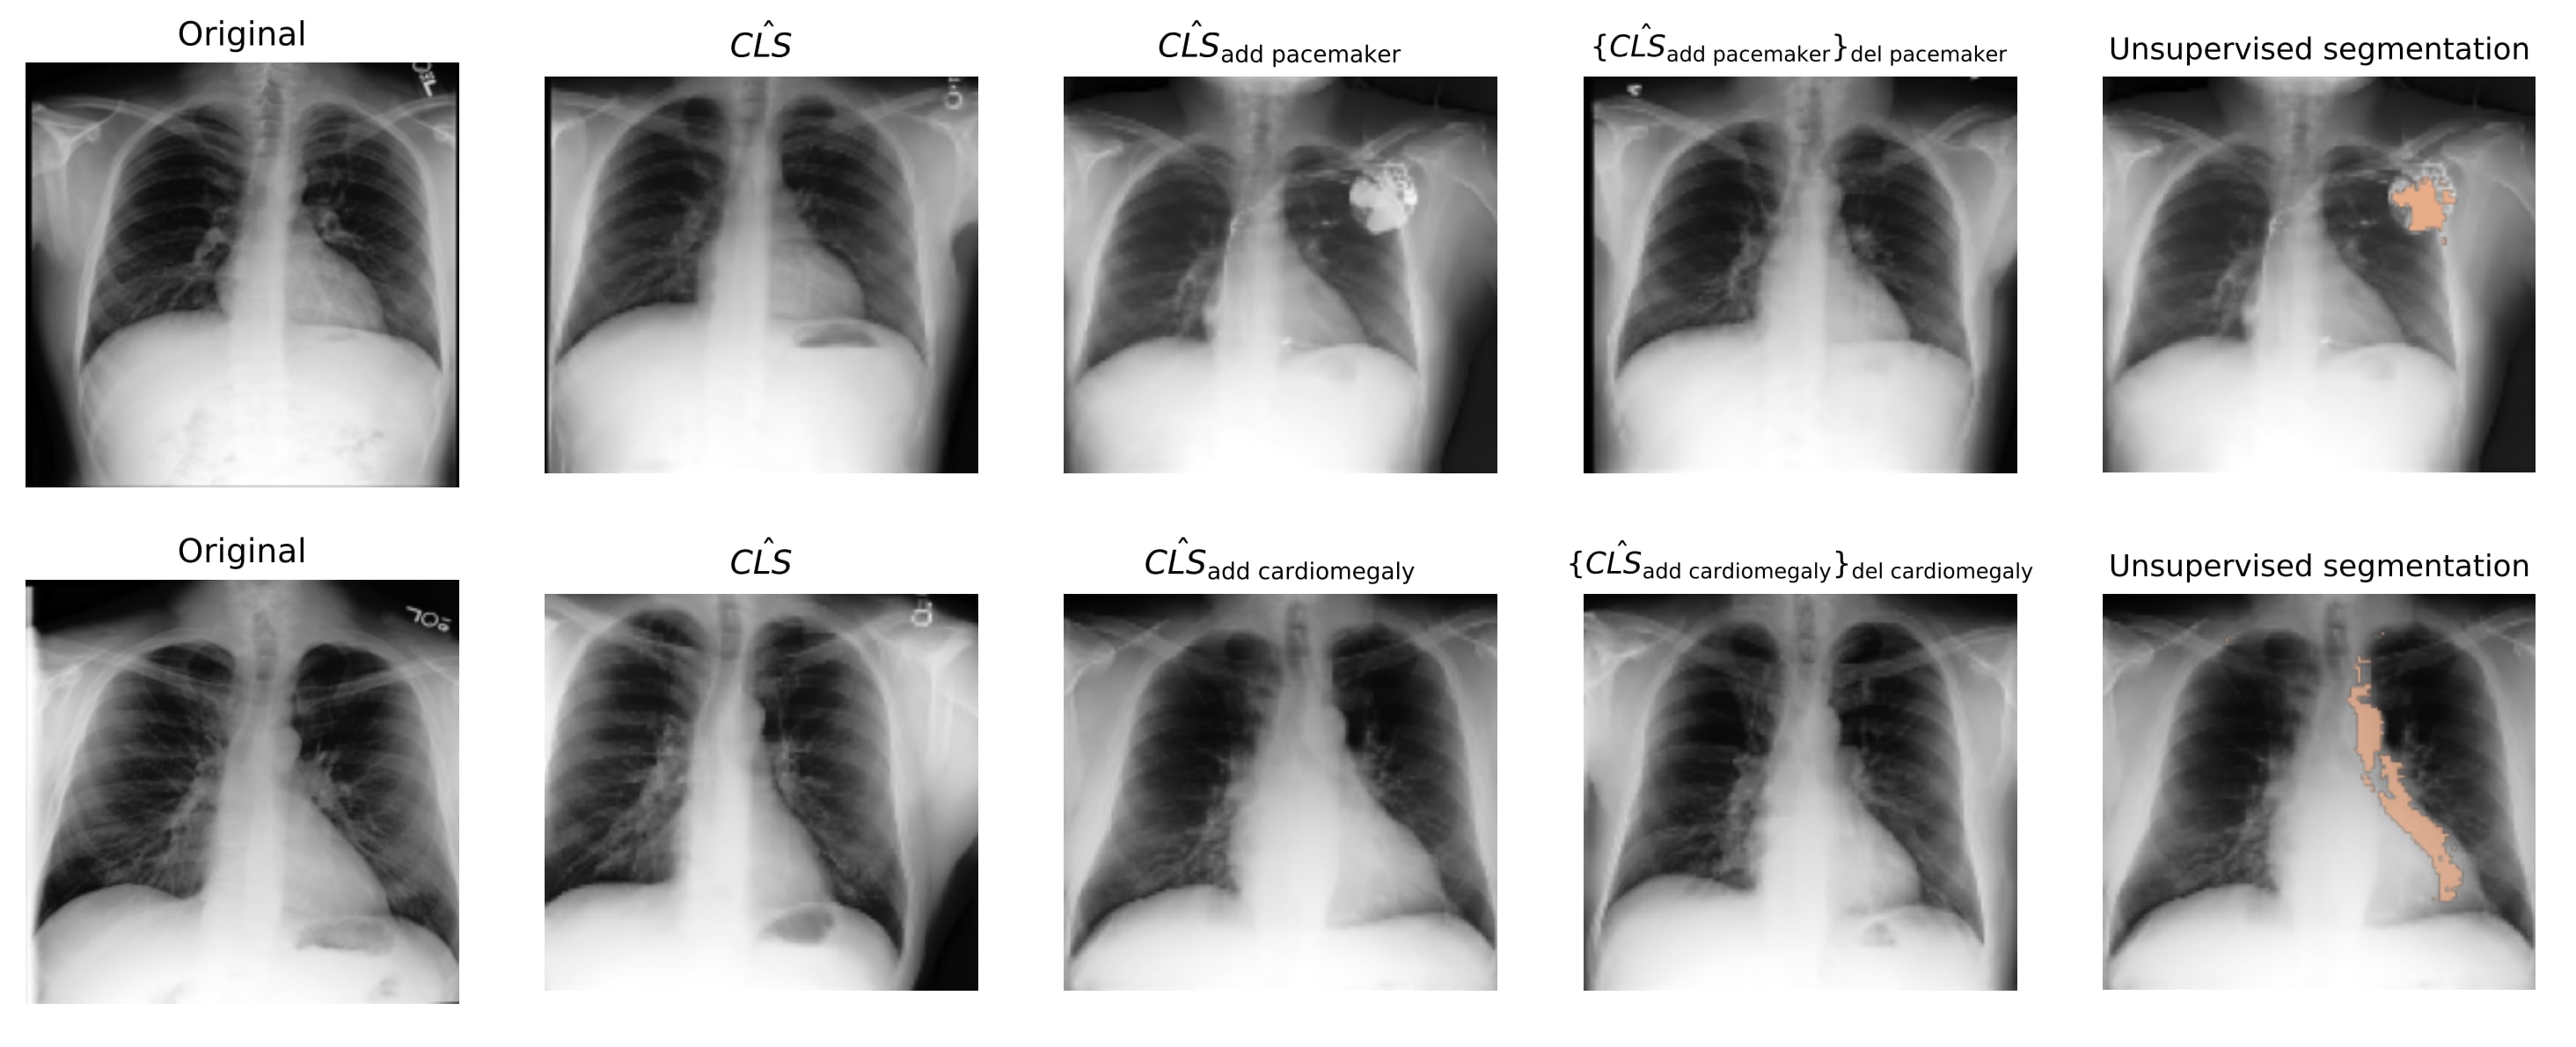

Counterfactual Image Generation